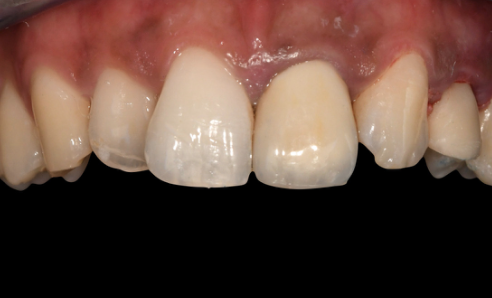

Screw-retained temporary crown seated — buccal view Screw-retained temporary crown seated — occlusal view

Final result The screw-retained temporary crown seated immediately after implant placement. The patient leaves the appointment with a fixed tooth in place from day one.

Step 6 — Immediate temporary restoration. A VARIOtemp abutment was placed, and a screw-retained temporary crown (designed by the lab in Dentalwings software and milled pre-operatively) was fitted immediately. A tunneling technique with a collagen membrane and porcine-origin hydroxyapatite was used to encourage bone regeneration and maintain the papillae.